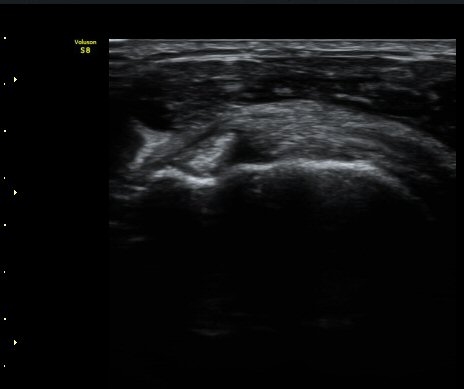

À­ÆÈÀ» ³»È¸Àü, ³»ÀüÇÑ »óÅ¿¡¼­ ±Ø»ó°Ç Á¾´Ü¸é°Ë»ç¿¡¼­ ±Ø»ó°Ç ³»Ãø¿¡¼­ ƯÀÌ ¼Ò°ßÀ» º¸ÀÌÁö

¾ÊÀ¸³ª(±×¸² 5) ±Ø»ó°Ç ¿ÜÃø¿¡¼­ ´ë°áÀý ÇÇÁú°ñ ¿¬°á¼º ¼Ò½ÇÀ» º¸ÀδÙ(±×¸² 6). ±ØÇ졂 Á¾´Ü¸é

°Ë»ç»ó(±×¸² 7) ƯÀÌ ¼Ò°ßÀ» º¸ÀÌÁö ¾Ê´Â´Ù. ±Ø»ó°Ç Ⱦ´Ü¸é °Ë»ç»ó ±Ø»ó°ÇÀÇ ±ÙÀ§ºÎ¿¡¼­´Â

ƯÀÌ ¼Ò°ßÀ» º¸ÀÌÁö ¾ÊÀ¸³ª(±×¸² 8) ±Ø»ó°Ç ¸»´ÜºÎÀ§¿¡¼­ ´ë°áÀýÀÇ °ñ °áÇ̰ú ÇÇÁú°ñ ¿¬°á¼º